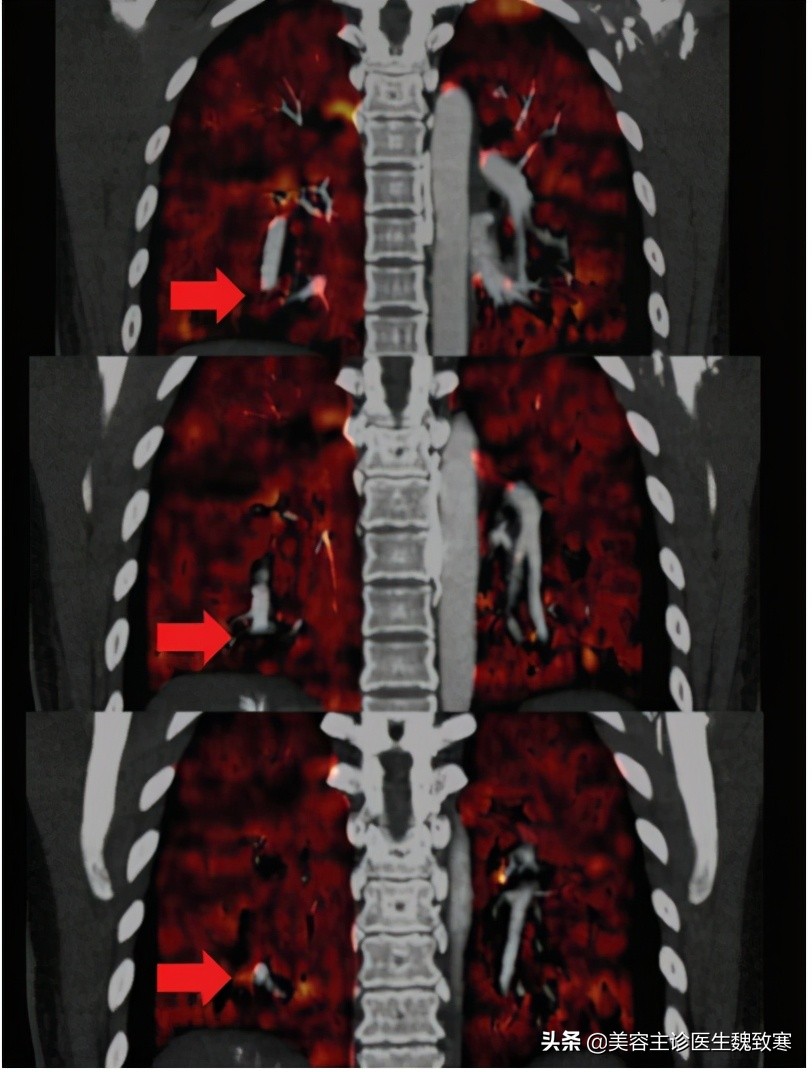

患者无吸烟或饮酒史,胸部听诊显示肺部大部分为双侧湿罗音。胸部计算机断层扫描(CT)显示左肺下叶局部渗出(见上图1),右心房(图2A)和心室增大,双侧下叶动脉发育不均伴充盈缺损(图2B)。

图2A、图2B

肺CT血管造影和三维重建显示右下叶后基底段肺动脉分支持续中断(图3)。经胸超声心动图显示心功能基本正常,无瓣膜异常。

图3